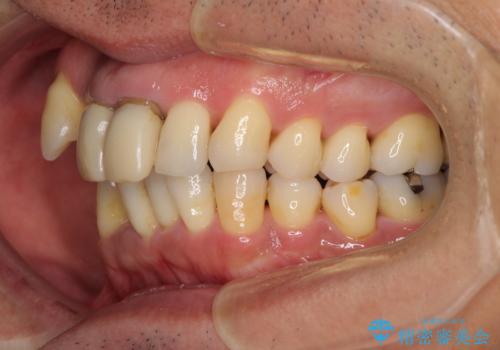

- 八重歯を気にして来院された患者様です。

上顎前歯の突出感と右上の八重歯を気にされていたので、上顎左右の第一小臼歯2本を抜歯し、ワイヤー装置にて矯正治療を行うこととしました。